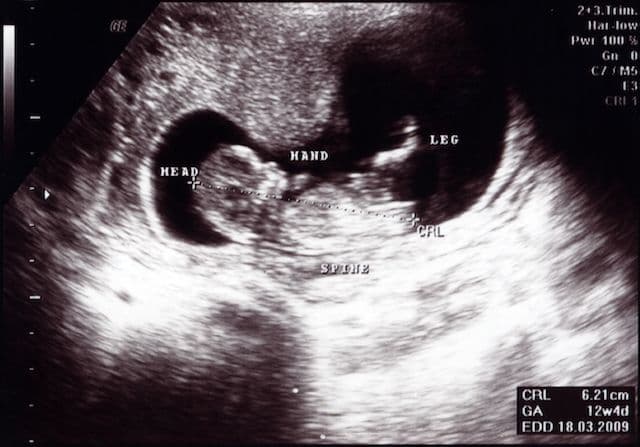

As you embark on your journey through pregnancy, understanding the fetal crown-rump length (CRL) is a powerful tool in monitoring your baby's development. In scientific terms, the CRL is the measurement from the top of the fetal head to the area just above where the legs begin, excluding the limbs and yolk sac. This crucial measurement is often captured through ultrasound, typically up until the 14th week of your pregnancy.